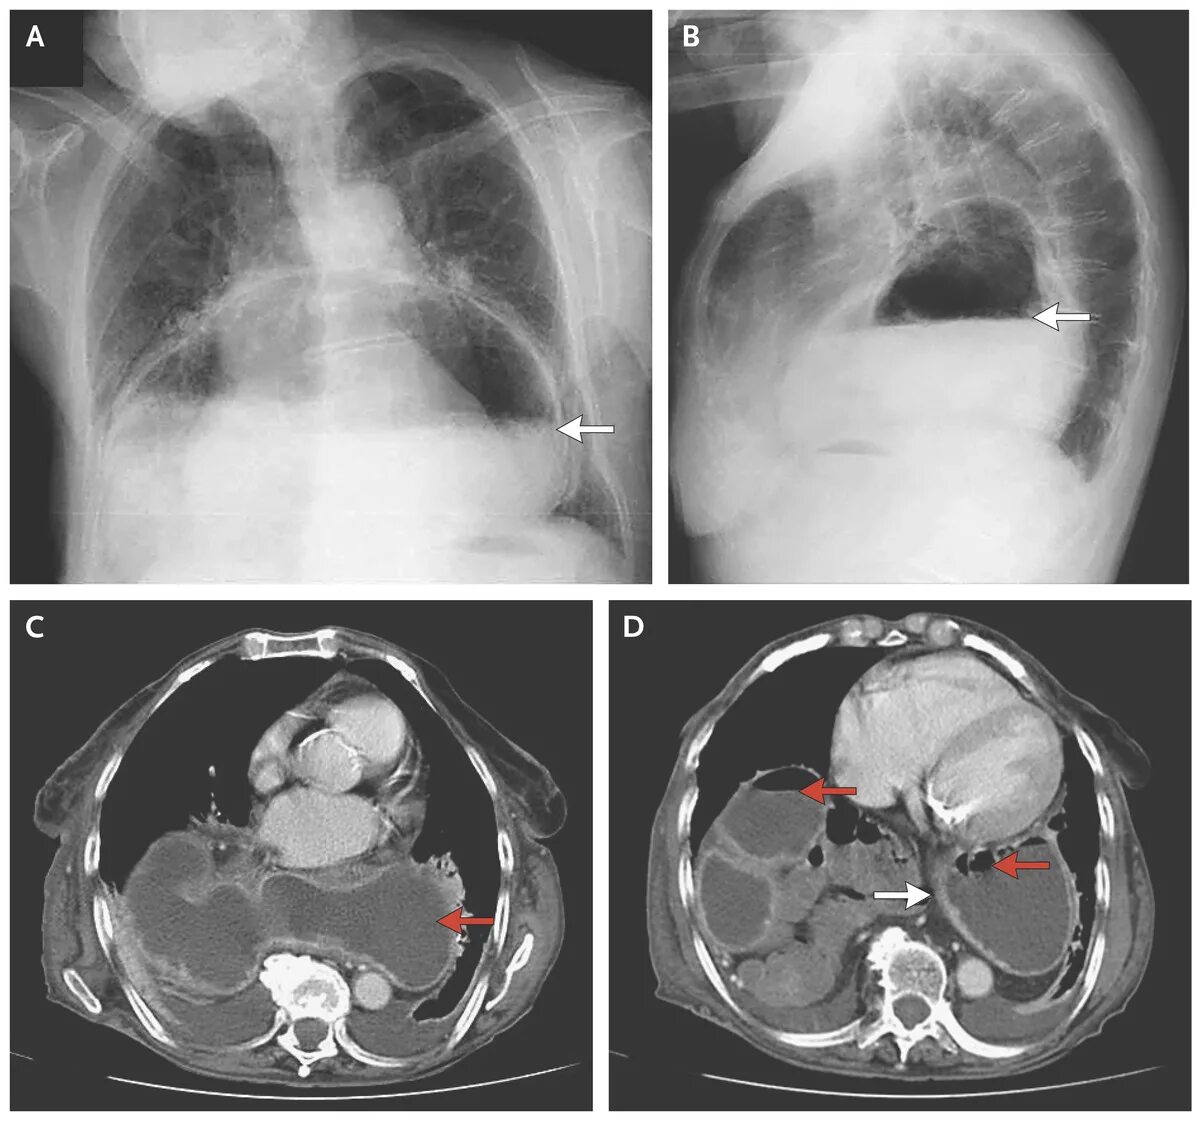

Диагностика диафрагмальной грыжи